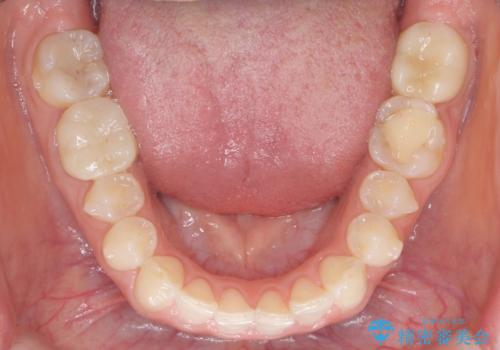

下の前歯のちょっとしたがたつきを治したい

- 下の前歯のがたつきを治したいとのことでした。

下の歯並びを並べるため、わずかに歯を削合しています。

そうしないと、前に出て上の前歯に強く当たってしまうためです。また、後戻りを防ぐ効果もあります。